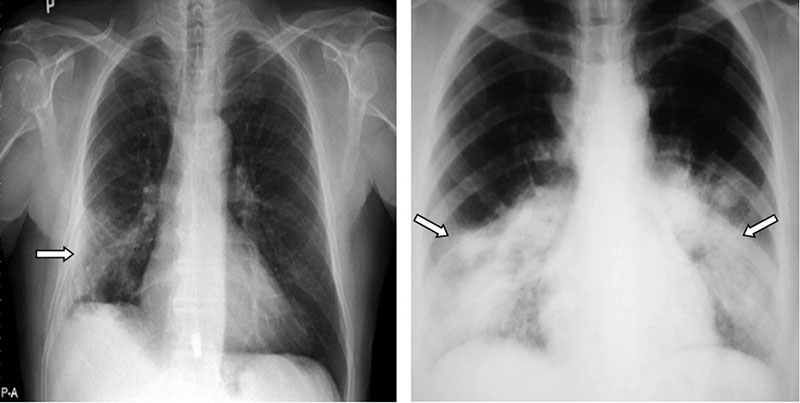

Xơ phổi là căn bệnh thường gặp hiện nay và nhiều người mắc phải. Vậy xơ phổi có nguy hiểm không và cách điều trị ra sao là câu hỏi của nhiều người. Xơ phổi là tình trạng các mô bên trong phổi bị tổn thương mãn tính khiến cho các mô phổi dày lên, cứng hơn do bị mất tính đàn hồi, từ đó gây ra sẹo. Phổi bị xơ sẹo và cứng nên làm hạn chế khả năng hít thở của người bệnh. Dưới đây chúng ta cùng...

Xơ phổi là tình trạng nhiều người gặp phải hiện nay và cũng có nhiều thắc mắc về căn bệnh này. Vậy xơ phổi là gì và cách điều trị ra sao là câu hỏi của nhiều người. Xơ phổi xảy ra khi các mô phổi bị tổn thương nhiều lần dẫn tới xơ hóa, ảnh hưởng và làm suy giảm chức năng của cơ quan này. Phổi bị xơ sẹo và cứng nên làm hạn chế khả năng hít thở của người bệnh. Dưới đây chúng ta cùng đi...